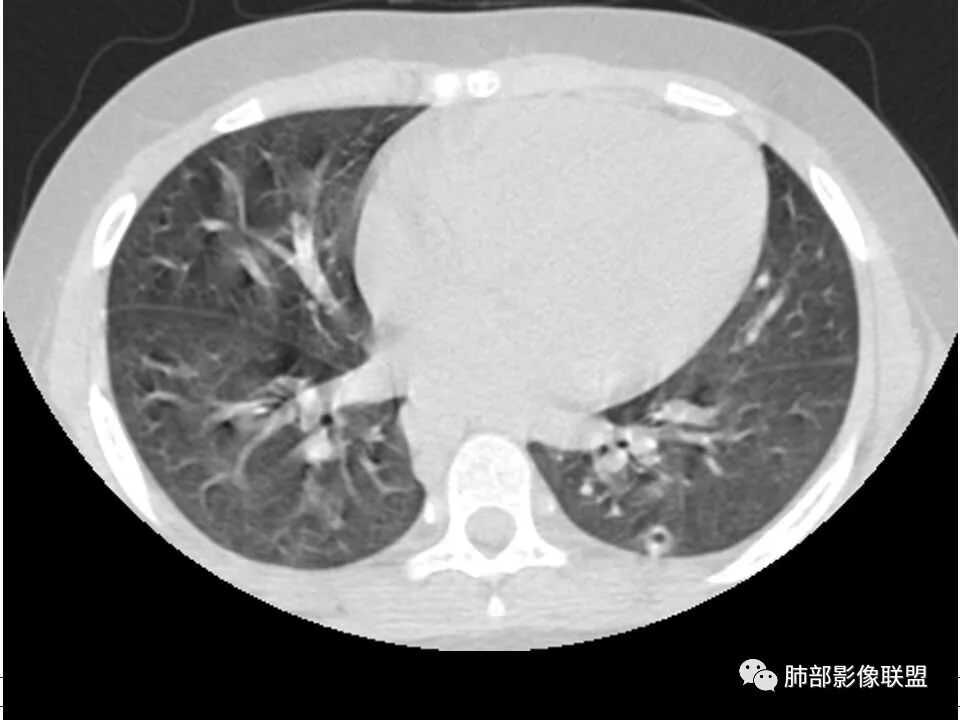

晨读,儿童,起病急,病程短,有下肢疼痛伴肿胀病史,发热,白细胞升高,结合下肢辅查,考虑骨髓炎,胸部ct:双肺多发空洞,结节,外带下叶为主,空洞内外光滑,无丝状物,有血管滋养征,综合病史及影像考虑脓毒性肺栓塞,金葡可能性大,建议痰培养,血培养,必要时ngs。

儿童患者,右下肢肿痛、发热起病,血象升高,双肺多发结节影,右肺结节并囊腔或空洞,左肺多发实性结节以胸膜下分布为主,考虑感染性病灶,有右下肢肿胀,需考虑蜂窝织炎, 血源性肺播散,金葡感染可能性大?

双肺多发空洞、结节及胸膜下楔形密度增高影,结合临床考虑:1.金葡菌肺感染。2脓毒性肺栓塞。

双肺多发结节,空洞,与胸膜相连,血道来源,空洞内壁光滑,结节周围模糊,考虑金葡菌感染。

患者儿童,因右下肢疼痛伴肿胀14天就诊。病程中有发热及伴随症状。膝关节MRI提示右侧膝关节及右髌骨髁异常信号影,右膝髌上囊及关节腔内少量积液。胸部CT:双肺胸膜下多发结节影,部分结节空洞形成,且结节周围可见血管集束征。综合考虑血源性脓毒性肺栓塞、坏死性肺炎。右侧骨髓炎、血播性金葡菌肺炎,鉴别其他特殊感染及血管炎。

胸部ct:双肺多发空洞,结节,外带下叶为主,空洞内外光滑,有血管滋养征,综合病史及影像考虑脓毒性肺栓塞,结合病史,金葡可能性大。

小儿,急性起病,下肢疼痛,mr提示骨髓水肿,临床化验炎性指标高,考虑金葡菌骨髓炎,双肺多发结节,以血管支气管束及胸膜下分布为主,部分结节近端与血管相连,部分结节可见空腔,内壁光整,部分囊腔有张力,考虑骨髓炎并肺内血播感染,金葡?

2.双肺多发片影,随机分布,多空洞或囊腔,胸膜下多楔形影,气道未见受累等等符合脓毒血症影像学表现,尤其是金葡。

1. 多发胸膜下外周结节、< 3 cm 的楔形影和滋养血管征 CT 表现;

4.经恰当的抗生素治疗,肺部浸润影吸收。滋养血管征为一支血管影连接肺部周边病灶,在 2/3 以上患者出现,可作为高度提示 SPE 的征象。